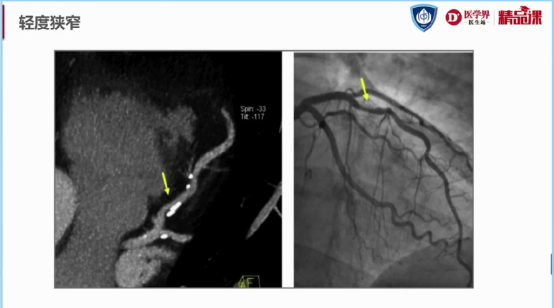

图7:轻度狭窄(25%-49%)示意图